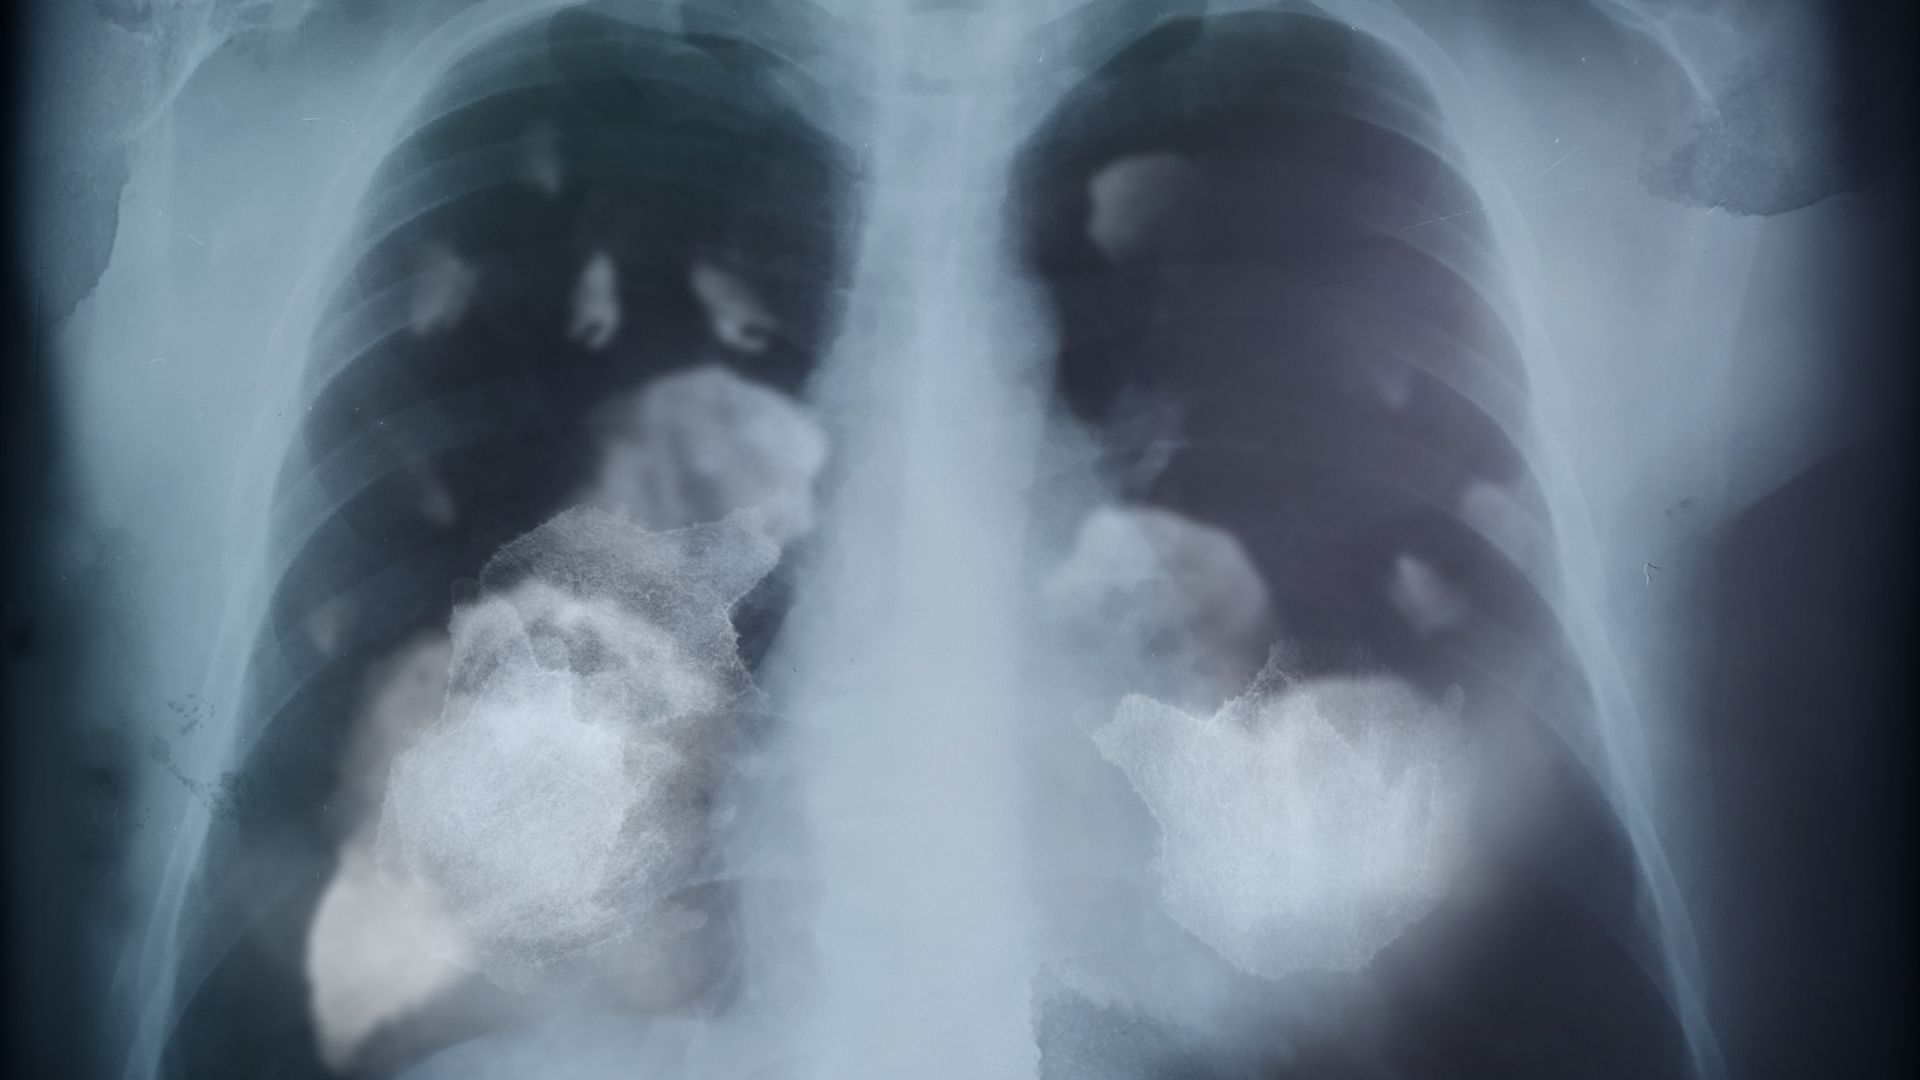

Trong giai đoạn muộn, hình ảnh phổi cho thấy mức độ tổn thương nghiêm trọng và lan rộng. Khối u có thể chiếm phần lớn nhu mô phổi, làm biến dạng cấu trúc giải phẫu ban đầu. Một số trường hợp ghi nhận tràn dịch màng phổi hoặc phổi bị xẹp, khiến khả năng trao đổi khí suy giảm nghiêm trọng.

Những hình ảnh ở giai đoạn này thường gây ấn tượng mạnh và cho thấy rõ tính chất nguy hiểm của bệnh. Chức năng hô hấp bị ảnh hưởng nặng nề, chất lượng cuộc sống của người bệnh giảm sút đáng kể. Đây cũng là giai đoạn việc điều trị gặp nhiều khó khăn hơn so với giai đoạn sớm.

Sau khi quan sát các giai đoạn tiến triển, không ít người cảm thấy ám ảnh trước những hình ảnh phổi bị tổn thương nặng nề. Điều này xuất phát từ việc các hình ảnh trực quan cho thấy rõ sự phá hủy dần dần của một cơ quan đóng vai trò sống còn trong cơ thể.

Hình ảnh phổi ung thư phản ánh quá trình mô phổi lành bị thay thế bởi các khối u bất thường, làm mất đi chức năng trao đổi khí. Khi nhìn thấy những vùng phổi bị đặc, xơ hóa hoặc biến dạng, người xem dễ nhận ra rằng đây không chỉ là một bệnh lý thông thường mà là tình trạng có thể đe dọa tính mạng nếu không được phát hiện kịp thời.